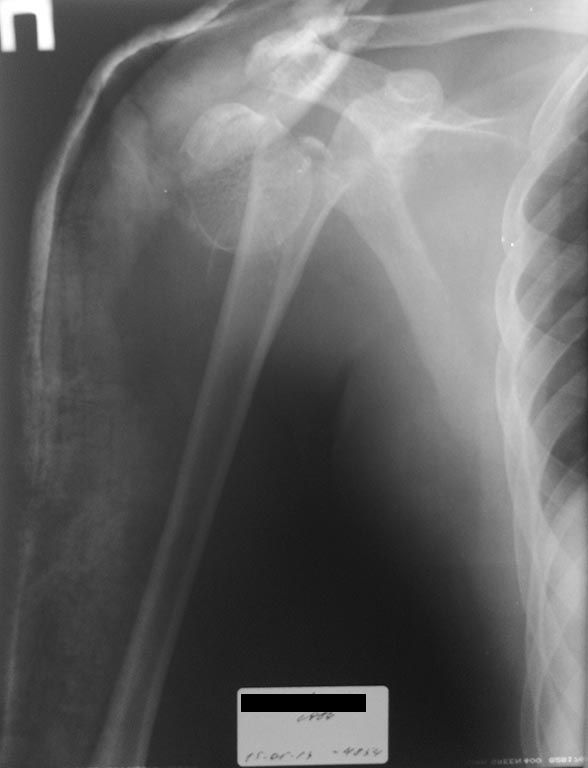

Сколько лет пациенту? При сочетанной травме скелетное вытяжение крайне нежелательно. Первым делом переведите голень на стержневой АВФ, или Илизарова. Оценка тяжести состояния, и в зависимости от него, необходимо восстанавливать плечевые кости. Этапно.Не пытайтесь прооперировать все в один день.Если другое плечо без вывиха головки, начните с представленного на снимке. Для шейки плеча предпочтительнее Phylos.О виборе импланта для голени судить нереально не видя снимка.

Перевести голень с вытяжения на стержневой АВФ(проще и быстрее) или Илизарова. В зависимости от тяжести состояния, оперировать, этапно, шейки плечевых костей. Предпочтение Phylos. Начинать с той где вывих головки. В последнюю очередь вернутся к голени. Выбор импланта для голени без снимка дискутабелен.)

2.На плечо справа планируем остеосинтез блокирующими пластинами.

3. На плечо слева БИОС проксимальным стержнем.